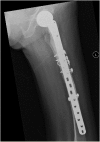

We report an 85-year-old patient with severe osteoporosis who had suffered from multiple episodes of periprosthetic fracture of the femur. Revision fixation with long-spanning cable plate for bisphosphonate-induced atypical periprosthetic femoral fracture was performed. Nonunion and implant failure occurred at 16 months requiring revision surgery using long-stem femoral prosthesis with cable-plate fixation. To further facilitate bone healing, allograft and bone morphogenetic protein (BMP) were added. Eventually bone union was achieved after one year.